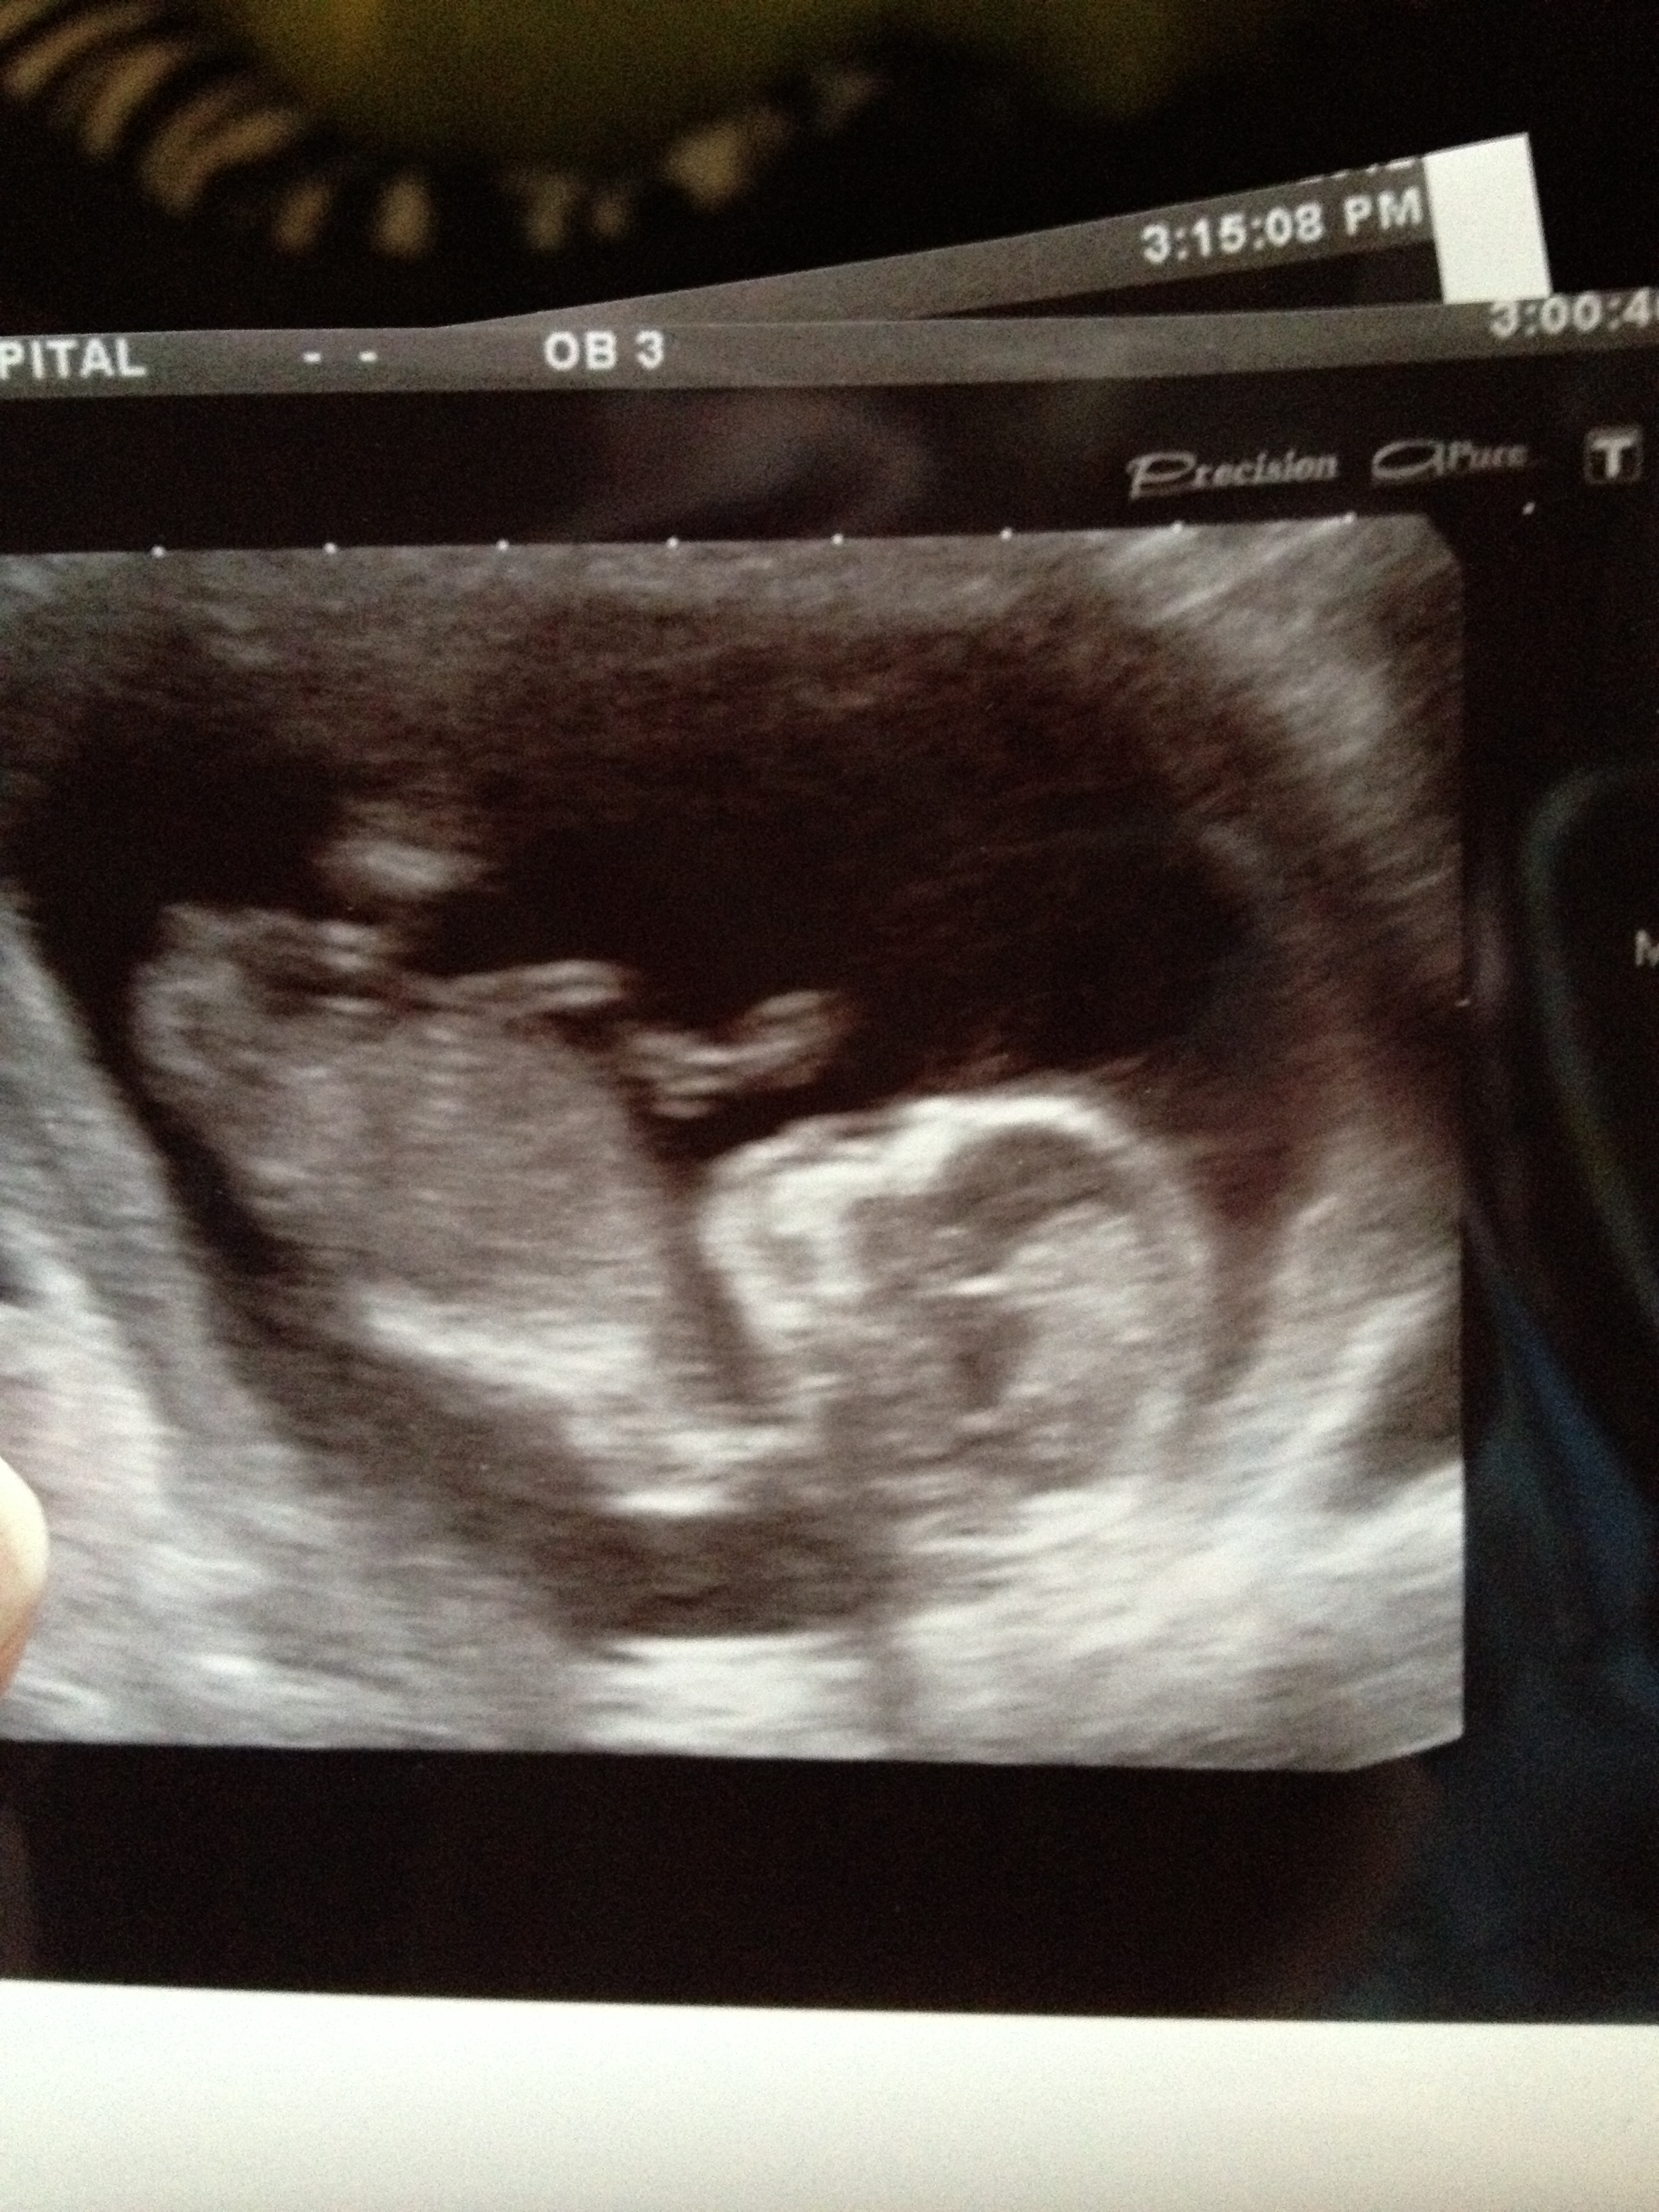

Attachment 3930Attachment 3930Attachment 3929my 1st baby and 9 weeks to go!!!! i didnt find out ! now wishing i had!!:) so any guesses xxxxxx

If what I think is the nub, then girl :)

I think Boy from skull...

The first 2 look girl but the third looks boy and skull looks boy... 50/50! You're so close to finding out your suprise!!

Boy by skull. GL

i'd say boy - i think i see a lil nubber in 2 of the pics. GL!

I guess boy